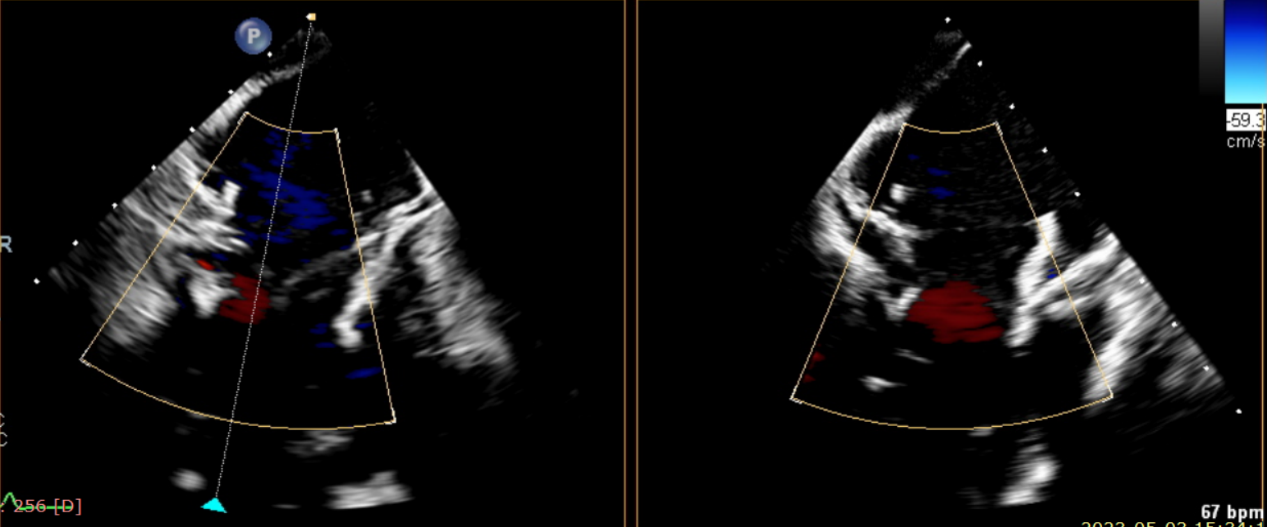

術(shù)后超聲提示無(wú)瓣周漏

術(shù)后超聲提示僅殘余輕微瓣周漏

術(shù)后Azeem Latib教授對(duì)LuX-Valve Plus經(jīng)血管三尖瓣置換系統(tǒng)的器械性能和治療效果大為稱贊,并且認(rèn)為L(zhǎng)uX-Valve Plus的手術(shù)體驗(yàn)非常好。從治療效果來(lái)看,術(shù)后即刻超聲顯示三尖瓣反流幾乎完全消失,血流動(dòng)力學(xué)改善顯著,患者恢復(fù)快。在面對(duì)復(fù)雜解剖結(jié)構(gòu)、超聲影像質(zhì)量不佳、有起搏導(dǎo)線干擾時(shí),Lux-Valve Plus也體現(xiàn)了極強(qiáng)的適應(yīng)性。Thomas Modine教授參與了術(shù)中指導(dǎo),他同樣再次肯定了LuX-Valve Plus術(shù)中操作的便捷性,認(rèn)為L(zhǎng)uX-Valve Plus容錯(cuò)率高,對(duì)術(shù)中影像的依賴小,并表達(dá)了后期希望可以更多地應(yīng)用LuX-Valve Plus三尖瓣置換系統(tǒng)于臨床實(shí)踐,讓更多的三尖瓣重度反流患者盡早獲益,改善預(yù)后。